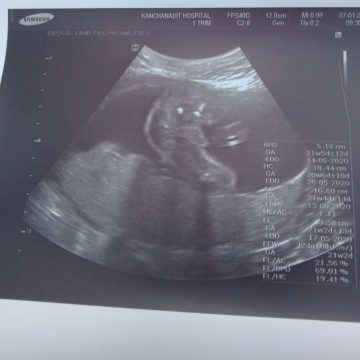

หญิงหรือชายค่ะ20wดูไม่ออก

ช่วยดูหน่อยค่ะ ญ/ช ค่ะ หมอบอกว่าชาย ถ้าชายแบบมันใหญ่แปลกจังค่ะ แม่สงสัยมาก😅

ใบซาวด์คุณแม่ก็เป็นแบบนี้ค่ะ 20w เท่ากัน หมอบอก ผช ค่ะ

เหมือนเห็นแหลมๆน่าจะชายนะแม่

น่าจะชายค่ะ ของบ้านนี้ชายค่ะ

เหมือนจู๋ ช ค่ะ

น่าจะชายค่ะ